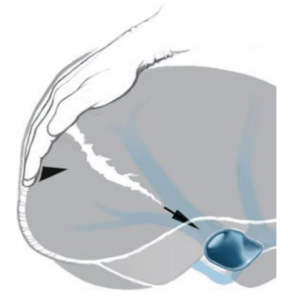

Trường hợp máu đã ngừng chảy thì chỉ cần lấy máu cục quanh gan, rửa sạch ổ bụng, đặt dẫn lưu (nếu cần). Trường hợp chảy máu nhiều từ gan có thể cầm máu tạm thời bằng cách ép gan bằng tay (Hình 2), ép gan với hai tay và ép vào cơ hoành, giao cho người phụ giữ, kiểm soát cuống gan toàn bộ (thủ thuật Pringle) (Hình 3), nhanh chóng thăm dò ổ bụng để loại trừ các nguồn chảy máu khác.

Hình 3. Thủ thuật Pringle và Kiểm soát toàn bộ mạch máu gan